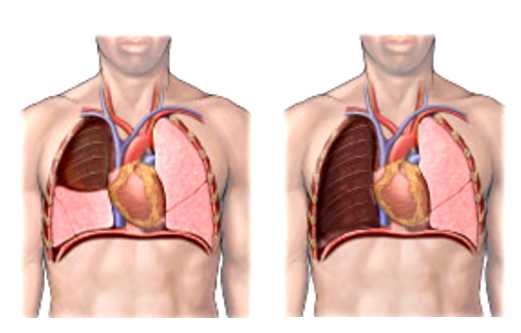

Π€ΠΎΡΠΎ 3 β ΠΠΎΠ±ΡΠΊΡΠΎΠΌΠΈΡ

Π€ΠΎΡΠΎ 4 β ΠΠ½Π΅Π²ΠΌΠΎΠ½ΡΠΊΡΠΎΠΌΠΈΡ